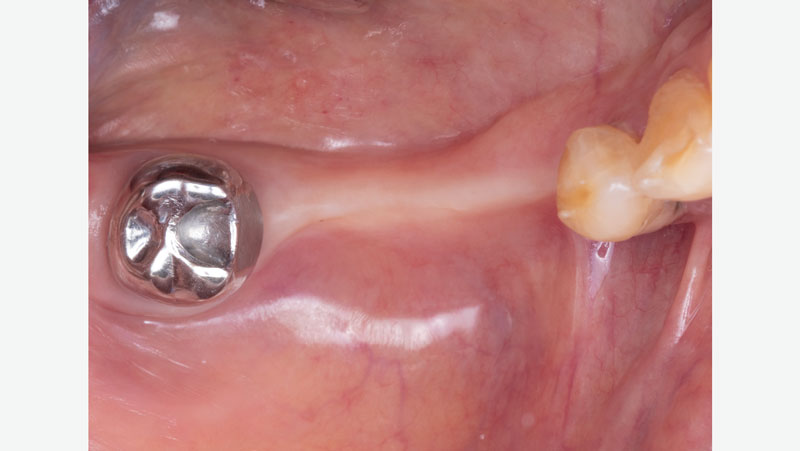

Occlusion-without-partial

Occlusion without partial

Ridge-spacing-without-partial

Ridge spacing without partial